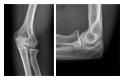

Primary and posttraumatic arthritis of the elbow

Whether degenerative joint disease of the elbow may be the result of primary or posttraumatic etiologies, arthritis of the elbow commonly leads to pain, loss of motion, and functional disability. A detailed history and focused physical examination, in combination with imaging modalities, can help localize the origin of symptoms and help direct treatment. Although nonoperative treatment is the initial therapy for arthritis of the elbow, surgical interventions may provide substantial relief to the appropriately selected patient.